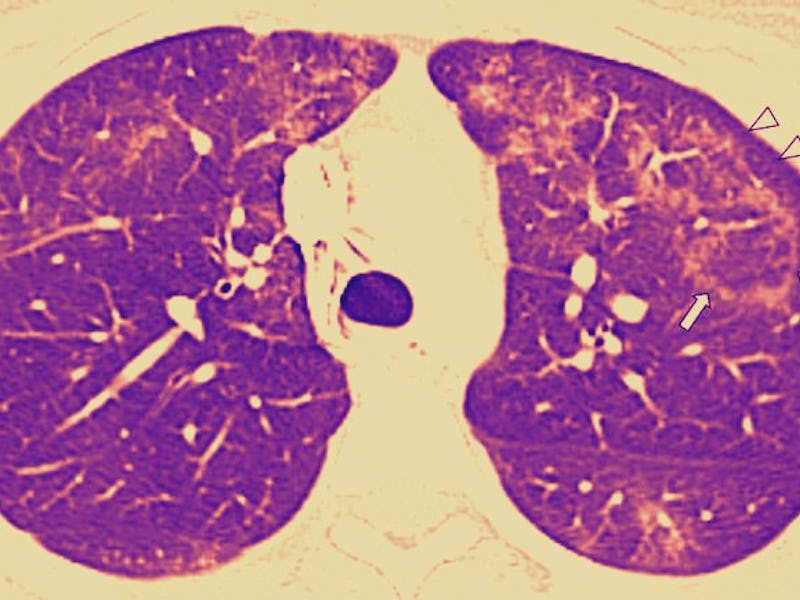

This is a scan of the axial lung window. It gives radiologists a look at the middle regions of the lungs. These lungs belong to a 16-year-old girl who, for one year, used both nicotine and THC-containing e-cigarettes, until she experienced acute abdominal pain. After a day of vomiting, she went to the hospital. The white triangles in the image point to ground-glass opacity, surrounded by the reversed halo sign. The arrows also point to subpleural sparing — a sign of lung abnormalities.

An axial lung window image of CT with contrast enhancement performed.

This CT scan of an axial lung window belongs to a 17-year-old boy. He used THC-containing e-cigarettes for two months until he experienced 8 days of nausea, vomiting, abdominal pain, and fever. Those symptoms were paired with subsequent chest pain and shortness of breath. The arrows point to the presence of central ground-glass opacity, surrounded by the reversed halo sign.